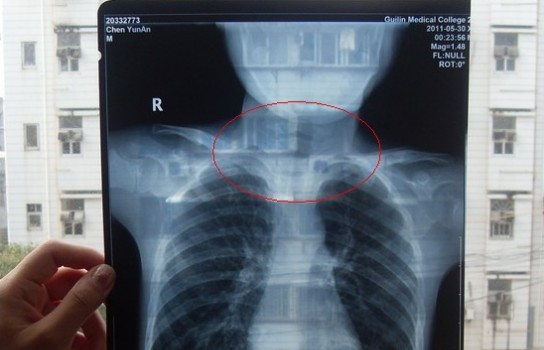

桂林市民陳先生的孩子患病,醫院需拍攝X光來確診。但陳先生認為,桂林醫學院附屬醫院(以下簡稱醫學院附院)拍攝時不按規范操作,會影響孩子正常成長發育。為此,陳先生將該醫學院告上法庭。8月27日,秀峰區法院對此案進行了調解,但陳先生覺得不合理,準備上訴到桂林中院。

胸部正位X光片圖

2011年5月29日下午,陳先生的兒子安安出現嘔吐、肚子疼痛等癥狀。陳先生立即將兒子送往醫學院附院,根據醫生開出的會診單,分別對安安做了腹部立臥位2次和胸部正位1次共3次X光片檢查、診斷。醫生看X光片后排除了腸梗阻病因,判斷是闌尾炎。經過治療,不久安安身體痊愈。

可是,陳先生的一次偶然發現,讓他們一家過上了提心吊膽的日子。因為,在安安出院一個月后,陳先生偶然翻出孩子治療期間的X光片。發現在X光片中,孩子的生殖器官以及甲狀腺等敏感部位也在被放射區域中。而陳先生上網查到:人體拍攝X光片是有一定輻射的,并且輻射有可能引起基因變異等問題,他立馬陷入恐慌中。

至于,為什么拍攝X光時,孩子的敏感部位也在放射區域內,這讓陳先生百思不得其解。為此,他專門到醫學院進行了質疑。而醫院的醫務人員說,拍腹部X光片就要照到睪丸,要檢查睪丸是否正常,而且怕小孩亂動,所以要照寬些。

但陳先生對此說法難以理解,當年6月30日他向桂林市衛生局衛生監督所投訴。在陳先生提供的桂林市衛生局復函中,記者看到上面寫明了是醫學院違法了《放射診療管理規定》。為此,陳先生要求醫學院對此行為道歉并且進行補償,不過醫院方拒絕補償……無奈之下,陳先生只好在2012年5月底將醫學院附院告上法庭。

6月19日,秀峰區法院依法開庭審理此案。法院認為雖然醫學院附院診療行為違規,可是根據桂林市疾控中心提供的數據,原告的孩子3次X光拍攝過程中,全身輻射累積吸收劑量對身體不會造成不良影響,所以駁回陳先生的賠償請求。并在8月27日組織雙方進行調解,但陳先生對調解方案不認可。

因為,陳先生始終覺得桂林市疾控中心給出的數據有錯誤。“我兒子只有六歲多,他們不調整照射范圍,這是不負責的行為。并且,在放射科里面明明有防輻射服,醫生竟然不提醒我們穿,我真的很怕這些對小孩身體有不好的影響,如果影響到后代的基因,我不知道找誰說理去。” 于是,他決定向桂林市中級人民法院遞交上訴狀。